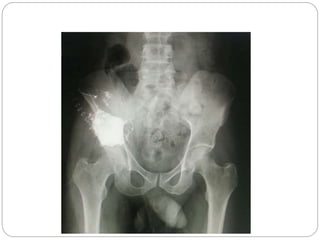

This document discusses 8 oncology cases. Case 1 involves a 40-year old female with right knee pain. Case 2 is a 28-year old male with a left subtrochantric fracture from a MVA who is now experiencing increasing left knee pain and swelling. Biopsy results showed high-grade osteosarcoma. Case 3 is a 30-year old female with breast cancer and bone metastases causing bilateral hip pain.